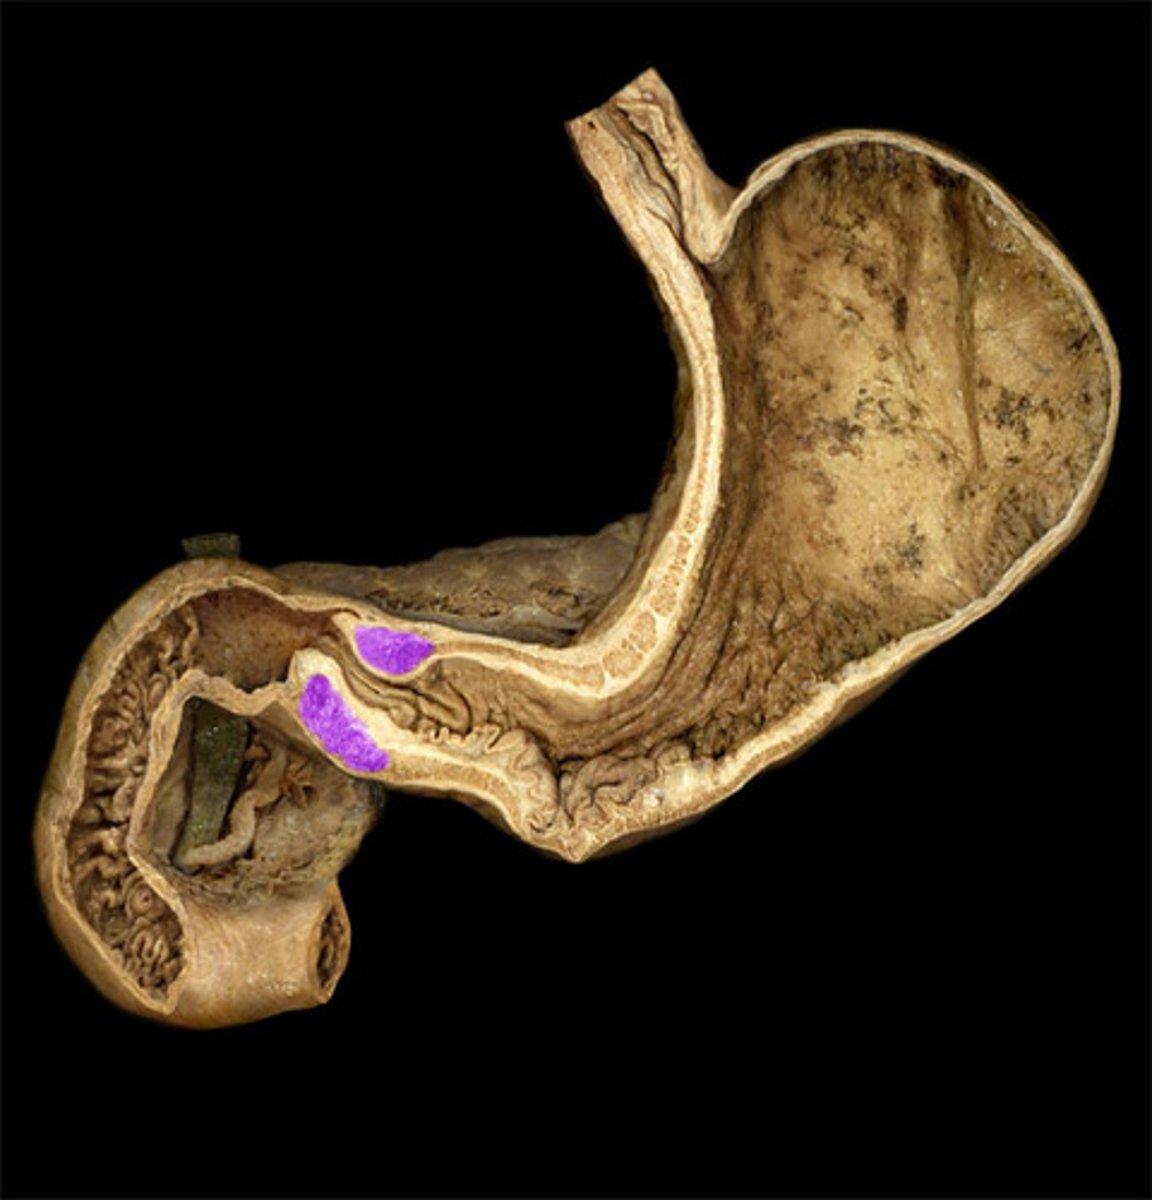

What is this?

Cardiac region of stomach

Fundus

Body of the stomach

Pylorus

Pyloric sphincter

Greater curvature

Lesser curvature

What are the 4 parts of the duodenum?

Upper

Descending

Horizontal

Ascending

Jejunum

Ileum